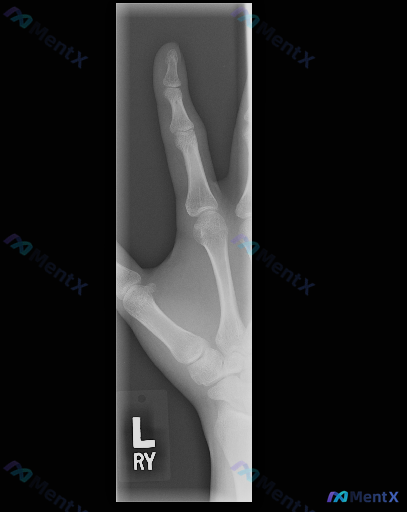

整理到一份左手斜位X光的影像分析资料,常规阅片结论其实是“左手中指及对应掌骨骨骼结构完整,关节间隙对位良好,未见明显外伤性骨折、退行性骨关节病或骨质破坏的影像学证据”。 但这份资料同时设定了一个反向讨论前提——假设“存在异常”,需要重新审视每一处骨皮质边缘、髓腔密度及软组织窗。 如果是你拿到这张“阴...